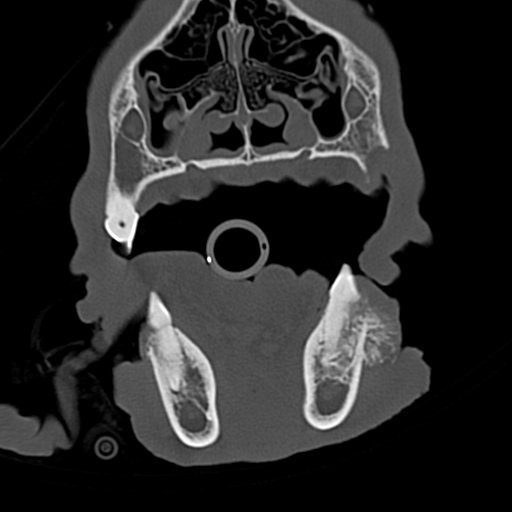

Die Heilungsaussichten sind sehr gut, wenn der Tumor vollständig mit dem Zahnhalteapparat entfernt wird. Es ist nicht erforderlich, extrem viel Gewebe um den Tumor herum zu entfernen. Die genauen Operationsgrenzen wurden vor der Operation durch eine Computertomographie bestimmt. Dieses Verfahren lässt die Knochenstruktur sehr gut erkennen. So lässt sich sehr viel genauer als mit einem Röntgenbild beurteilen, wie weit die Veränderung reicht. Der Tumor lässt sich anhand dieses Befundes komplett entfernen.